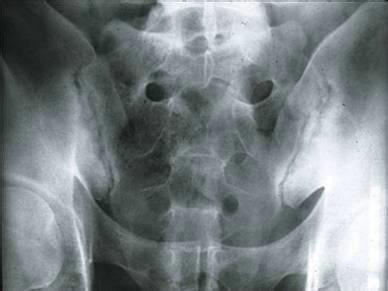

来自新乡市卫滨区的姜同学是一名强直性脊柱炎患者,来到我院(郑州痛风风湿病医院)后,自述3年前开始病发,他的父亲也是一名强直性脊柱炎患者,12岁之前,他一直为自己没有遗传父亲的强直而庆幸。可是就当...[详细]

来自郑州市惠济区的赵先生来到我院(郑州痛风风湿病医院)后,自述曾身患强直性脊柱炎3年,听说强直是不治之症后,一直接受中药治疗,可疗效不佳。2014年10月,看到各大新闻媒体对我院的介绍,让赵先生满怀...[详细]

来自郑州市管城区的季同学来到我院(郑州痛风风湿病医院)后,自述患有强直性脊柱炎后,一直积极接受治疗。在经过2年的无效治疗后,季同学心生绝望,终日消沉。到了2018年6月,季同学的病情加重,经过不断寻找...[详细]